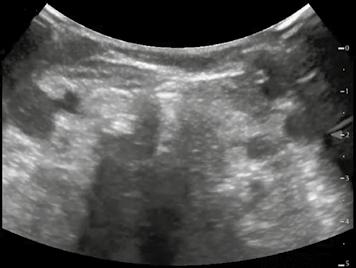

Von freier abdomineller Flüssigkeit (FAF) spricht man, wenn sich im Ultraschall echofreies Material im Bauchraum (intraperitoneal) findet. Normalerweise ist in der Bauchhöhle keine Flüssigkeit zu erwarten, d. h. der sonografische Nachweis von freier intraabdominel ler Flüssigkeit ist immer als pathologisch anzusehen. Freie Flüssigkeit muss aber nicht in jedem Fall Blut sein. Freie Flüssigkeit aufgrund einer anderen Vorerkrankung wird auch als „Aszites“ bezeichnet. Aszites ist Flüssigkeit, die entweder aktiv in die Bauchhöhle sezer niert wird oder passiv aus den Gefäßwänden austritt.

Abb. 34 ˘ Morison-Pouch (1) zwischen Leber (2) und rechter Niere (3). Rechtsseitiger Flankenschnitt 1 2 3

Abb. Abb.

44 4 ˘ Pathologische Befunde

36 ˘ Douglas-Raum (1) dorsal der Blase (2). Unterbauchlängsschnitt

35 ˘ Koller-Pouch (1) zwischen Milz (2) und linker Niere (3). Linksseitiger Flan kenschnitt 3 2 1 21

Die Unterscheidung zwischen einer Blutung in die Bauchhöhle und einer anderen Ursa che der FAF ist präklinisch oft nur anhand der Wahrscheinlichkeit möglich. Für eine end gültige Diagnosesicherung ist eine Punktion notwendig. Oft hilft aber der gesunde Men schenverstand – bei einem akut außerorts mit dem Motorrad verunglückten jungen Mann mit freier abdomineller Flüssigkeit ist ein Aszites durch Leberzirrhose nicht unbedingt die wahrscheinlichste Diagnose.

Zunächst sammelt sich mögliche freie Flüssigkeit an drei typischen präformierten Stel len im Bauchraum und kann hier sonografisch dargestellt werden. Dies sind der MorisonPouch, der Koller-Pouch und der Douglas-Raum (von engl. „Pouch“ für „Beutel“, Abb. 34 –36).

Der Morison-Pouch ist eine Aussackung des Peritoneums zwischen Leberunterrand und rechter Niere. Dem entspricht auf der Gegenseite der Koller-Pouch zwischen Milz und linker Niere. Der Douglas-Raum befindet sich dorsal hinter der Harnblase und zieht bis ins kleine Becken.

Findet sich die Flüssigkeit nicht „frei“, sondern als echoarmer mehr oder weniger aus geprägter Saum zwischen Milz und Milzkapsel oder zwischen Leber und Leberkapsel, ist gerade bei einem Abdominaltrauma von einer (noch!) gedeckten Organruptur auszuge hen. Hier droht dann als zweizeitiges Geschehen die Ruptur der Kapsel in die Bauchhöhle mit folgender erheblicher Blutung.

Je nach Menge der freien Flüssigkeit ist in den beschriebenen Räumen ggf. nur eine schmale echofreie Lamelle zu erkennen, bei erheblichen Mengen freier Flüssigkeit ist diese aber auch im ganzen Bauchraum sichtbar. So sieht man bei Patienten mit fortge schrittener Leberzirrhose oftmals im ganzen Bauch nur noch „schwarz“, und darin einge bettet die parenchymatösen Oberbauchorgane ebenso wie den Darm.

Abb. 37 ˘ Freie Flüssigkeit (FAF) (1) im Morison-Pouch. Rechtsseitiger Flankenschnitt Abb. 38 ˘ Freie Flüssigkeit (FAF) (1) im Koller-Pouch. Linksseitiger Flankenschnitt

1 1